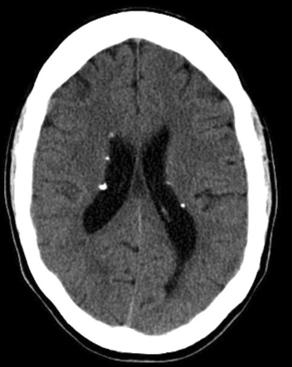

2. 结节性硬化

结节性硬化临床表现以皮脂腺瘤、癫痫和智力低下三联症为特征。病理特点为错构瘤,以室管膜下多发结节状钙化为主要特征性改变。